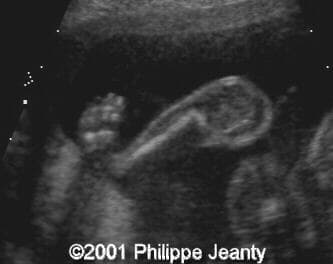

This fetus has a small amount of bowing and shortening of the right leg (compare to the left leg on the second image):

image19

image20